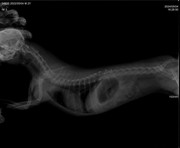

Коллапс трахеи форум